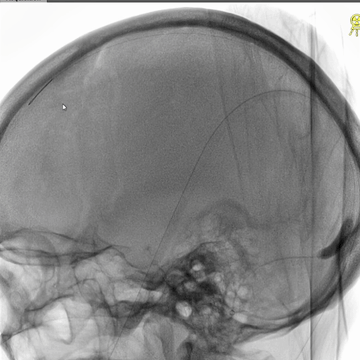

右侧颈动脉造影(正侧位):上矢状窦和直窦未见显影;右侧横窦和乙状窦少许显影。

左侧颈动脉造影(正侧位):上矢状窦前部少许显影,直窦未见显影,左侧横窦和乙状窦显影纤细。